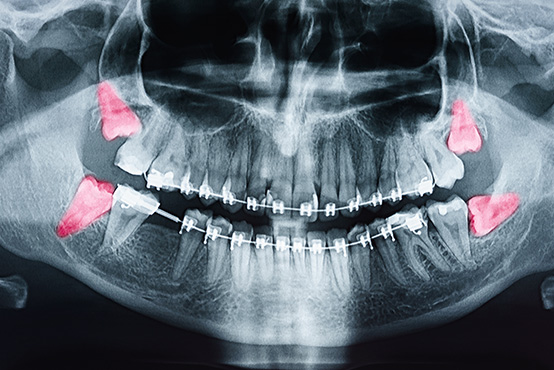

Dr. Linsky offers a comprehensive range of oral and facial surgical procedures, including dental implants, wisdom tooth removal, jaw surgery (orthognathic surgery), bone grafting, sinus lifts, TMJ treatment, and facial trauma care. Whether you’re seeking to restore missing teeth, correct jaw alignment, or relieve chronic pain, you can trust Dr. Linsky’s experience and precision. We combine advanced techniques with a personalized approach to help you achieve the healthiest, most functional, and most natural results possible.